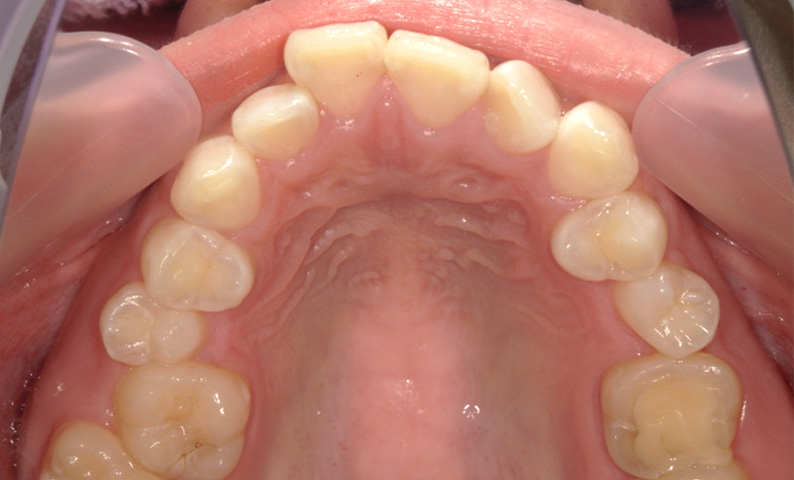

症例_010 「出っ歯」症例

治療期間:7ヶ月金額:30万円+税20代女性出っ歯捻転歯上の前歯だけ

| Before | After |

|---|---|

|